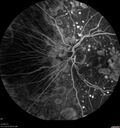

79 year old vision is in for a checkup with no visual complaints in the left eye. This is her better eye. VA 20/200 OD, 20/50 OS. 3 years ago she had a CRVO in the left eye. She is also diabetic for 20 years, has carotid insufficiency and anemia. Left eye shows CME. This was not treated and the vision improved to 20/40 over the next year although mild edema persisted.